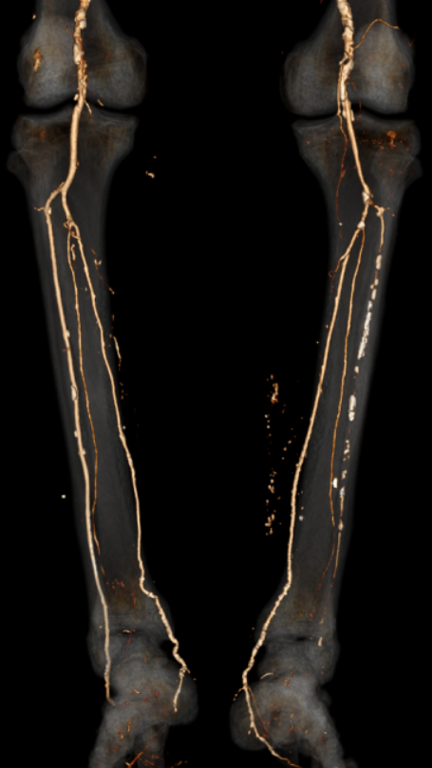

中山大学附属第一医院血管外科姚陈主任团队成功运用LiqMagic?P18外周血管内冲击波导管治疗一例下肢动脉硬化闭塞症患者。该患者为一名老年男性,患高血压和糖尿病20多年,并伴有慢性肾功能不全。因右脚持续疼痛1年多入院接受治疗。术前造影结果显示下肢多发动脉钙化,其中右侧股浅动脉、腘动脉、胫前动脉、足背动脉重度狭窄,并局部闭塞。

▲患者术前CTA